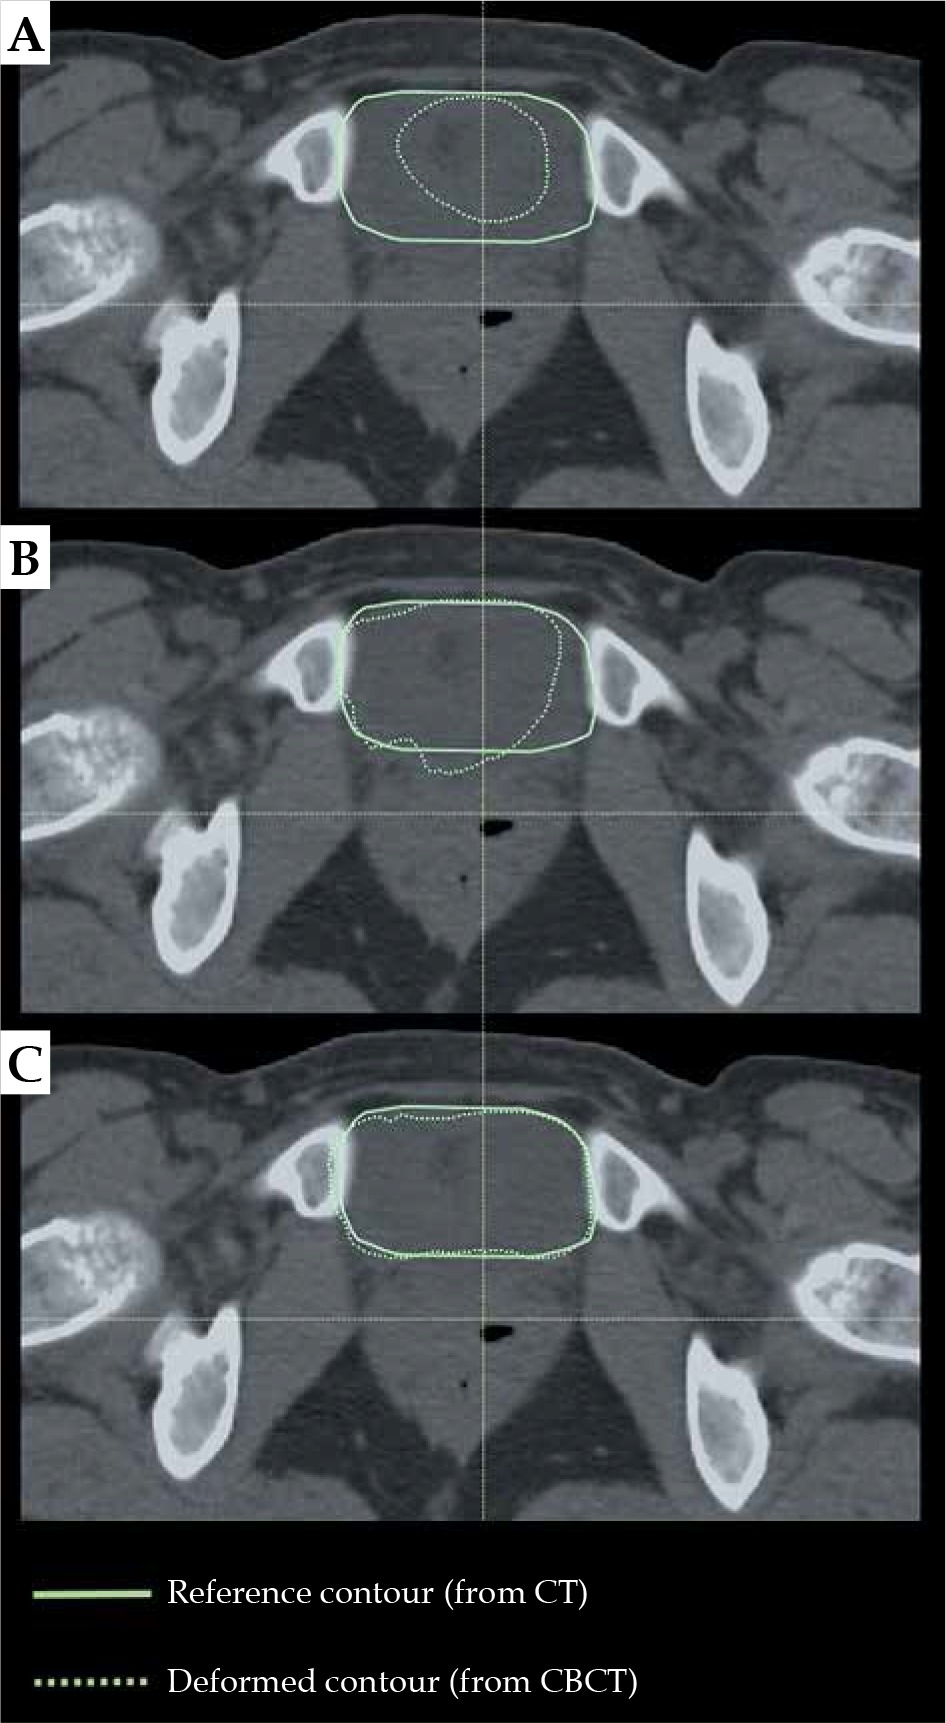

Image registration methods implemented in the RaySearch system enable both rigid and deformable registrations. As shown above, the deformable methods largely improve the quality of image registration as compared to the rigid methods (Figure 2). Evaluating the deformable methods, we demonstrated the biomechanical method to be the most effective one (Reg_3) (Table 2, Figure 3). Figure 6 shows the example alignment of bladder contours based on rigid registration (Reg_1) and deformable registrations: hybrid (Reg_2b) and biomechanical (Reg_3). A triangular mesh based on bladder contours was the control area for all registrations.

Fig. 6

Alignment of bladder contour from CBCT image (dashed line) with the corresponding reference contour delineated in the CT image (continuous line) for A) rigid registration, Reg_1, B) hybrid registration, Reg_2b, and C) biomechanical registration, Reg_3